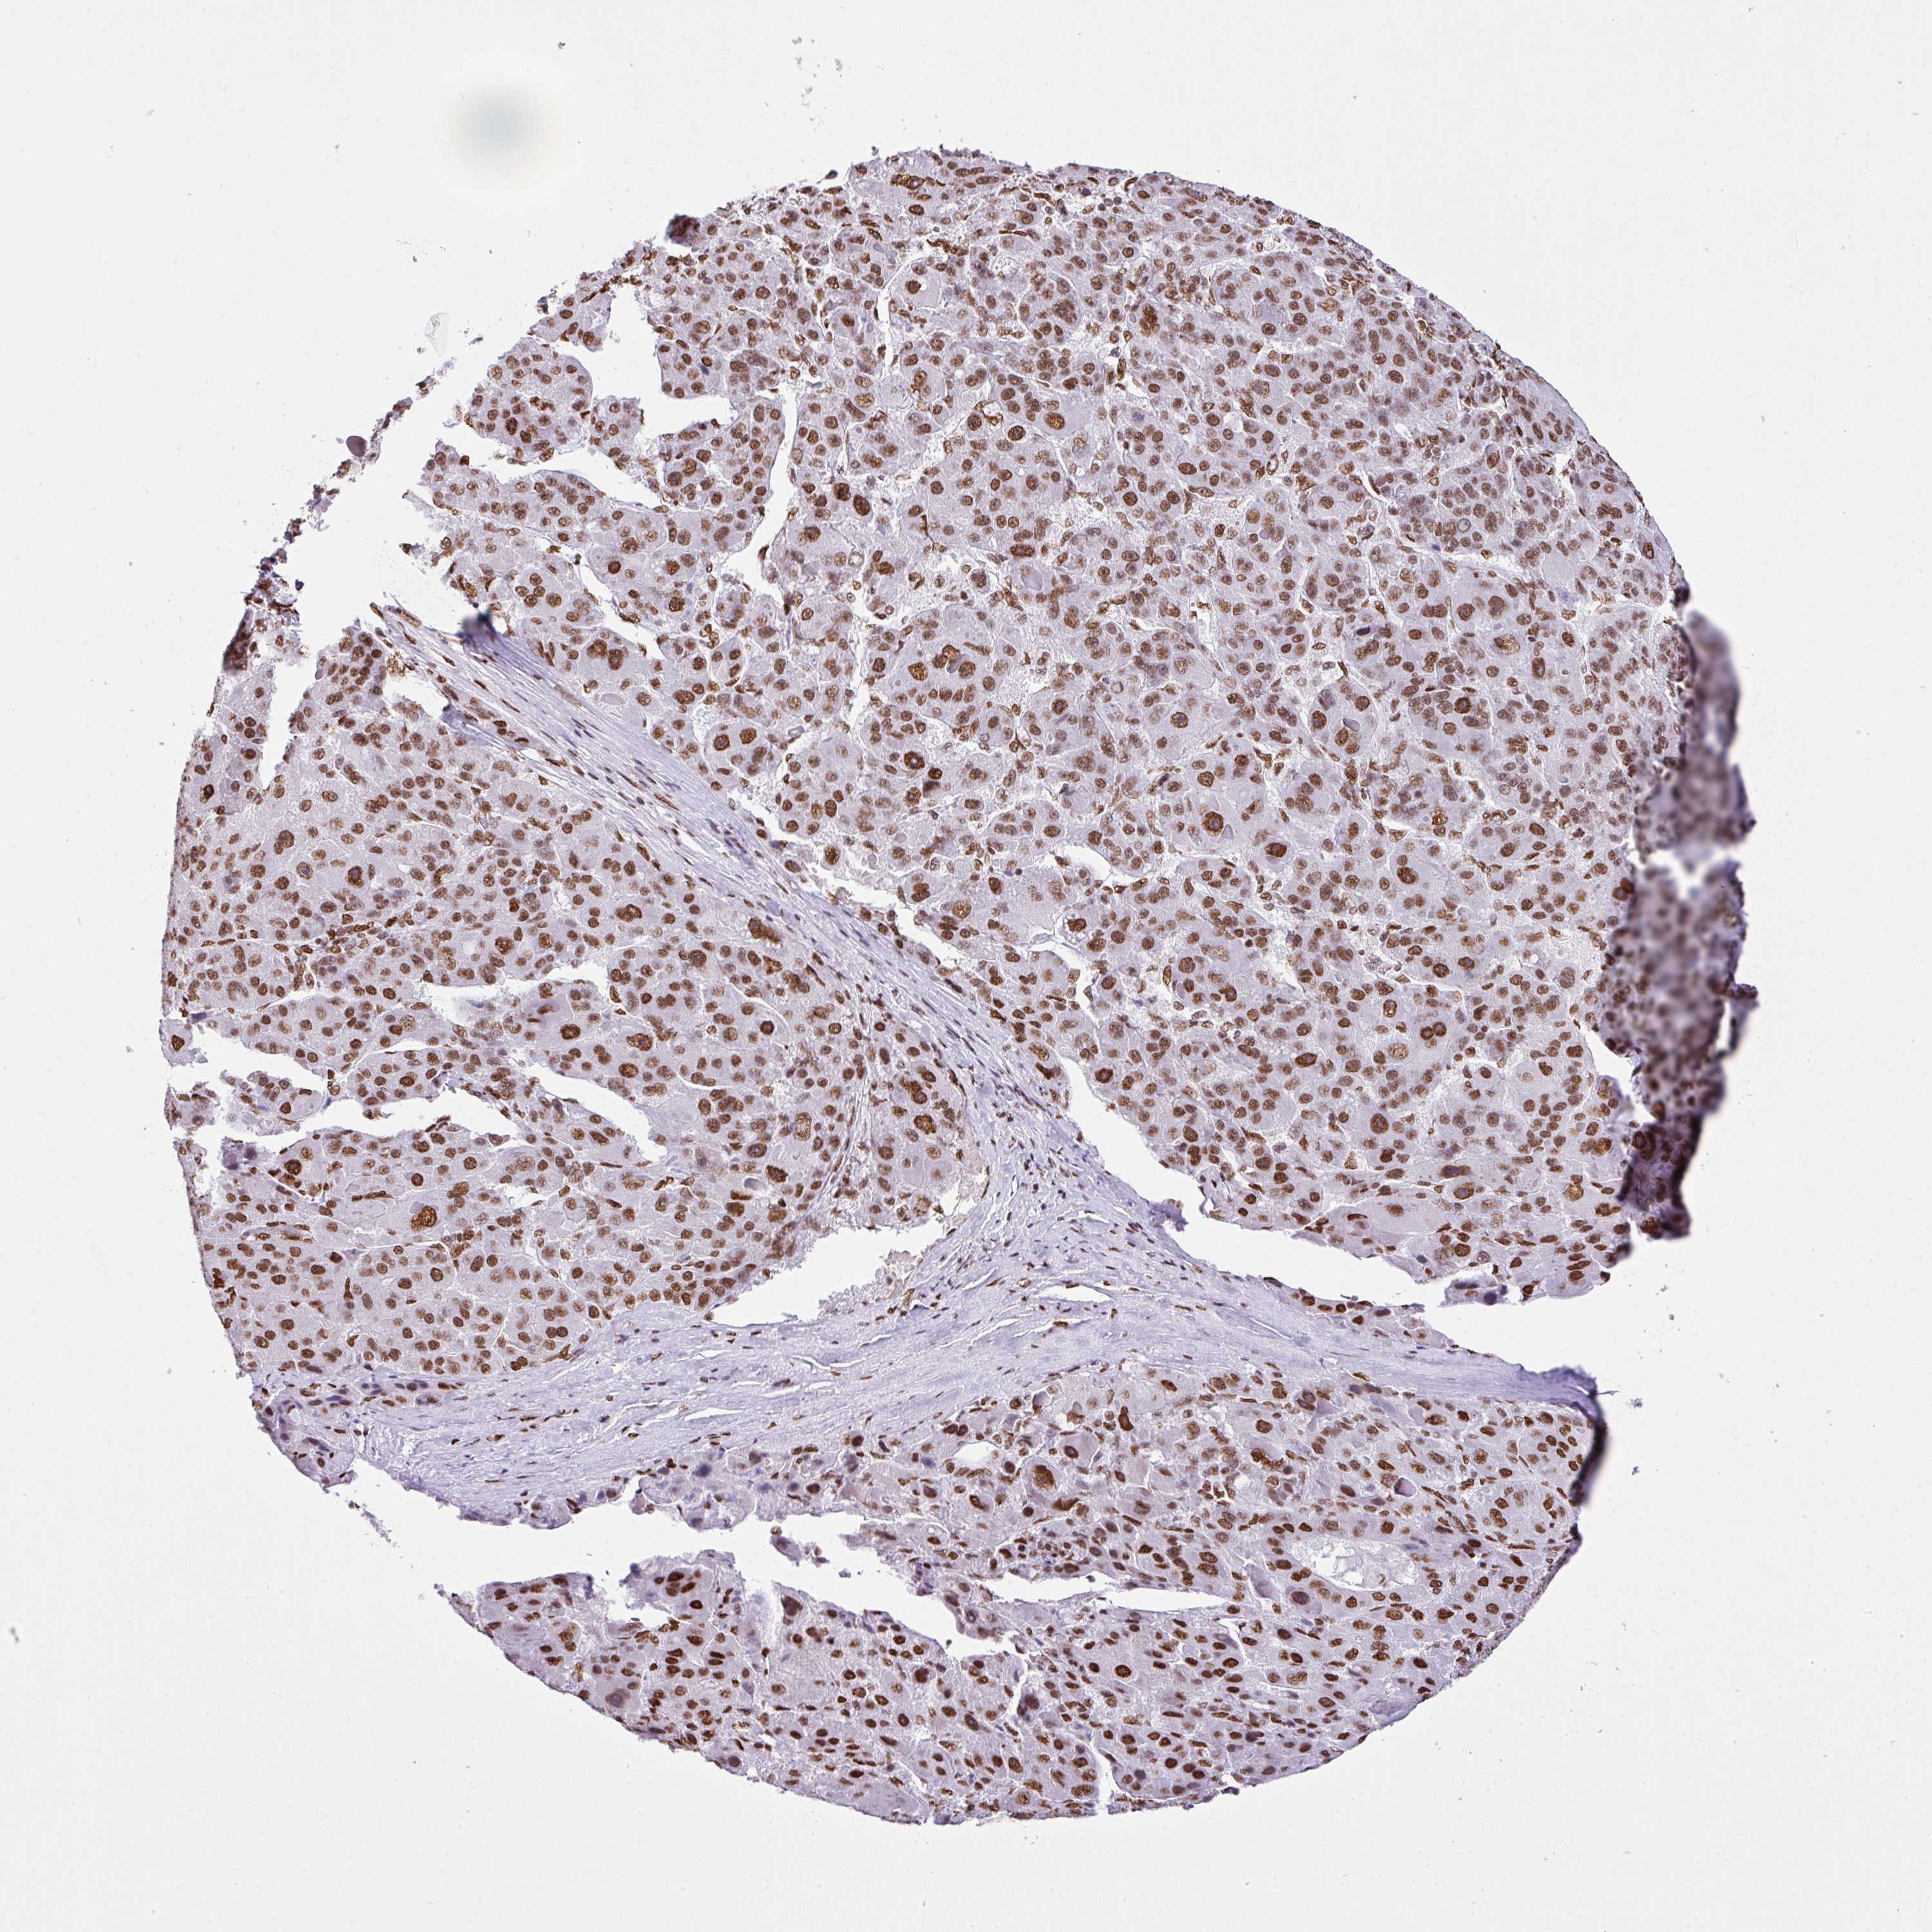

LIVER CANCER - Protein expressioni

A mouse-over function shows sample information and annotation data. Click on an image to view it in a full screen mode. Samples can be filtered based on level of antibody staining by selecting one or several of the following categories: high, medium, low and not detected. The assay and annotation is described here.

Note that samples used for immunohistochemistry by the Human Protein Atlas do not correspond to samples in the TCGA dataset.

Antibody stainingi

Antibody staining in the annotated cell types in the current human tissue is reported as not detected, low, medium, or high, based on conventional immunohistochemistry profiling in selected tissues. This score is based on the combination of the staining intensity and fraction of stained cells.

Each image is clickable and will lead to virtual microscopy that enables deeper exploration of all samples and also displays staining intensity scores, fraction scores and subcellular localization as well as patient and tissue information for each sample.

Antibody HPA053883

Staining

High

Medium

Low

Not detected

Intensity

Strong

Moderate

Weak

Negative

Quantity

>75%

75%-25%

<25%

None

Location

Nuclear

Cytoplasmic/membranous

Cytoplasmic/membranous,nuclear

Cholangiocarcinoma

Carcinoma, Hepatocellular, NOS